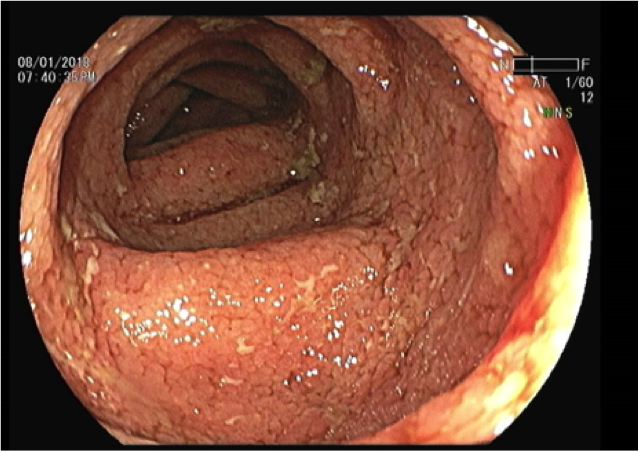

Las EII son una enfermedad crónica y progresiva del tubo digestivo que involucra periodos de crisis y estabilidad. La colitis ulcerosa es propia del colon y puede comprometer el recto y otros segmentos del colon, produciéndose por predisposición genética, alteraciones en el sistema inmunológico y en la microbiota intestinal. También inciden factores ambientales con el tabaquismo, el uso abusivo de antibióticos, el consumo de alimentos procesados y el estrés, que producen inflamación y lesiones en las mucosas del intestino.

La Enfermedad de Crohn afecta a distintas partes del tubo digestivo desde la boca hasta el ano y los síntomas incluyen dolor abdominal, diarrea, pérdida de peso, malestar, fiebre e incluso abscesos perianales. En cambio, se sospecha colitis ulcerosa cuando se presenta diarrea mucosanguinolenta, retorcijones y hasta un 90% de los pacientes con presencia de sangre en deposiciones.